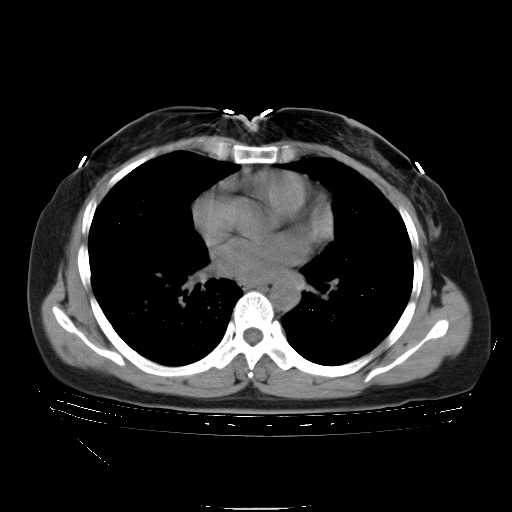

下面是今天刚刚做的,在上海治疗,吃了家属也说不清的一种药,一个月1万左右,

考虑  腺癌肺内转移,治疗较前病灶缩小、减少

肺癌并肺内转移,这种疾病治疗后在影像上看略有好转,不是很显著,但是肿瘤治疗效果影像只是一方面。

标准的细支气管肺泡癌呀!治疗后病情有所控制,也没治愈的迹象!

标准的癌性淋巴管炎!!距大去之日不远已.